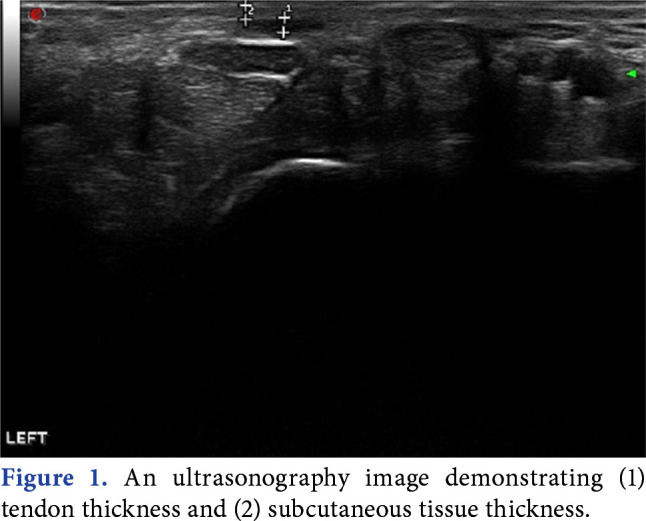

Objectives: This study aimed to evaluate the accuracy of four clinical tests confirmed by ultrasonography (USG) and to evaluate the role of age, sex, handedness, subcutaneous tissue thickness (STT), tendon thickness (TT), and STT/TT in determining the absence of the palmaris longus muscle.

Patients and methods: In this descriptive study, 282 wrists of 141 healthy individuals (71 females, 70 males; mean age: 29±9.6 years; range, 21 to 55 years) were included between September 2021 and November 2022. The palmaris longus muscle tendon was identified by Schaeffer's test, Mishra's test I, Thompson's test, and Pushpakumar's test and then evaluated with USG. Before the tests, age, sex, and dominant hand information of the individuals were obtained. The STT and TT were measured with USG.